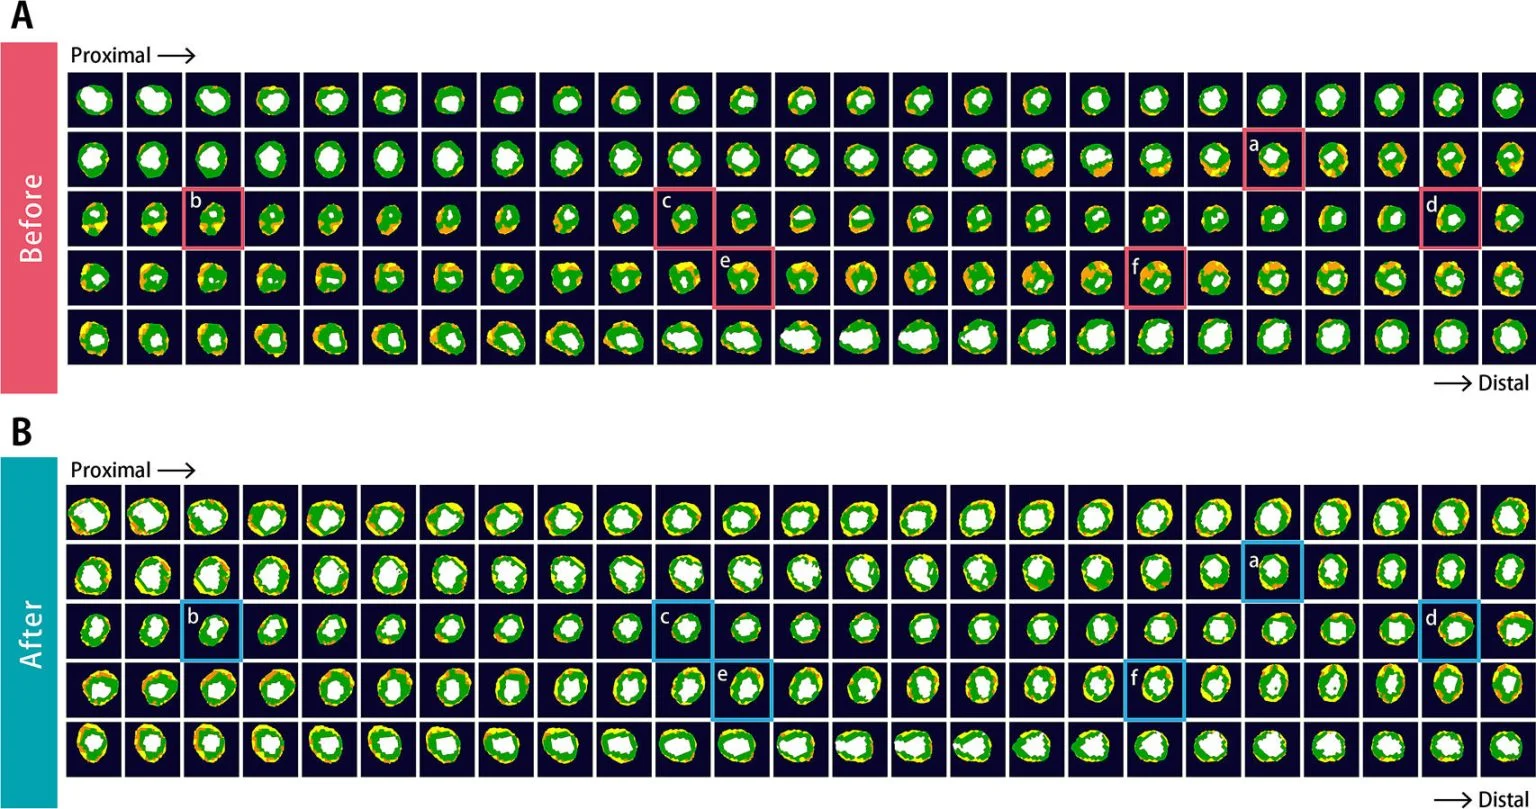

TGCV یا کاردیومیوواسکولاپاتی رسوب تریگلیسرید، یک اختلال نوظهور در سیستم قلبیعروقی است که با آترواسکلروز منتشر و باریک شدن عروق کرونری به دلیل رسوب تریگلیسرید شناخته میشود. این وضعیت ناشی از اختلال در تجزیه چربیها (لیپولیز) درون سلولهای عضلانی صاف عروق است و اغلب در بیمارانی دیده میشود که به درمانهای استاندارد پاسخ نمیدهند و معمولاً نیز تشخیص داده نمیشود. تصاویر A و B مربوط به دو بیمار در دهه شصت زندگی آنها هستند که از آنژین صدری مقاوم و دیابت قندی رنج میبردند. پس از تشخیص TGCV، هر دو بیمار مصرف مکمل غذایی تریکاپرین را آغاز کردند و علائم آنها ظرف چند ماه بهطور قابل توجهی کاهش یافت. تصویربرداری سیتیآنژیوگرافی کرونری در بررسیهای پیگیری، کاهش بارز ضایعات آترواسکلروتیک همراه با اتساع مجرای رگ را نشان داد (شریان کرونری چپ با خط قرمز در بالای تصویر A و شریانهای کرونری راست و چپ در بالای تصویر B). همچنین نواحی با تراکم پایین که از سمت خارجی رگ (آدونتیس) دیده میشدند (نواحی زرد و نارنجی در تصویر میانی A) و نیز حجم این نواحی (میلههای زرد در تصویر میانی B) کاهش یافتند که نشاندهنده کاهش مشارکت چربی در دیواره رگها است. این مشاهدات با افزایش لیپولیز میوکارد در اسکن ایزوتوپی با استفاده از ید-۱۲۳-بتا-متیل-پ-یودوفنیلپنتادکانوئیک اسید (پانلهای پایینی) همراه بود.

تصاویر سیتیاسکن محور کوتاه با کدگذاری رنگی، قبل از درمان با تریکاپرین (تصویر A) و پس از درمان (تصویر B) ارائه شدهاند. این تصاویر مربوط به شریان نزولی قدامی چپ قلب (LAD) هستند که در هر ۰٫۲ میلیمتر ثبت شدهاند. بخشهای a، b، c، d، e و f نمایانگر تصاویر مقطعی در تصویر دوم هستند و برای مقایسه دقیقتر قبل و بعد از درمان استفاده میشوند.